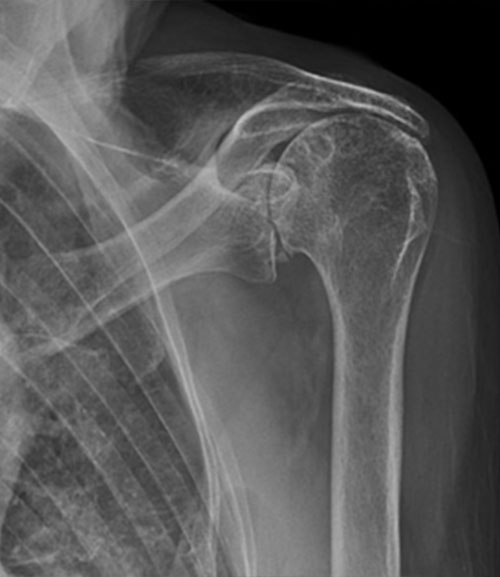

Plain x-rays will show evidence of arthritis and also what is described as “superior migration of the humeral head” in which the humeral head or ball of the shoulder can be seen sitting high in the glenoid because the rotator cuff is no longer able to hold it centred in the glenoid or socket.

Shoulder before reverse replacement surgery

Move the slider to compare cuff tear arthropathy and superior migration of humeral head with reverse prosthesis